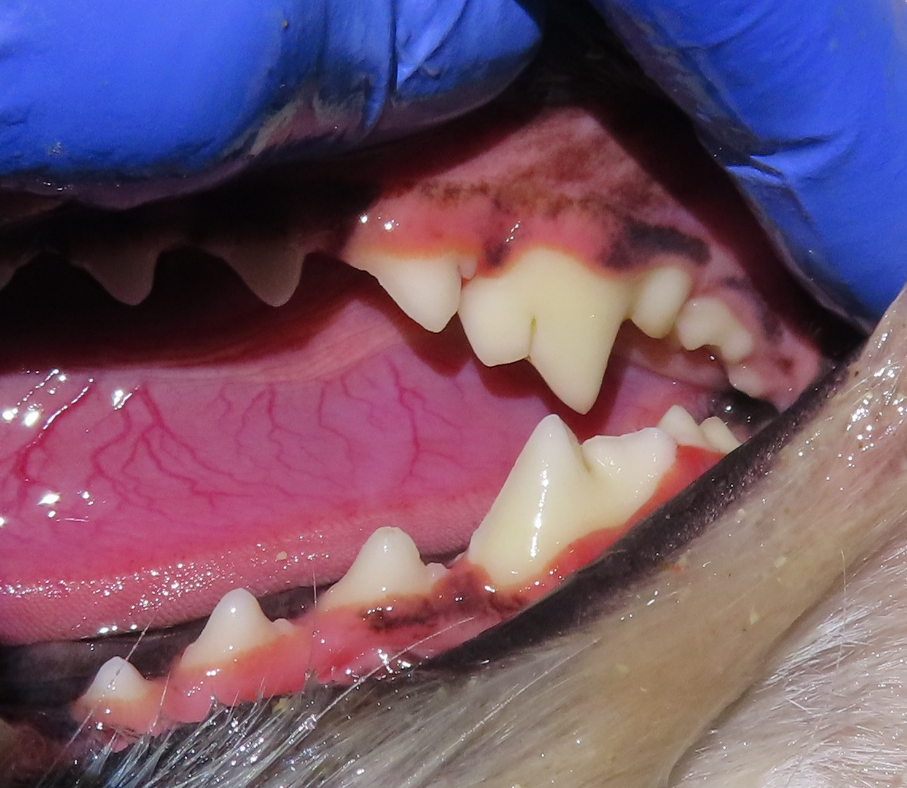

양치를 하다 보니 송곳니 뒤쪽 어금니의 잇몸 라인이 예전보다 내려가 보였고, 치아 표면도 살짝 깨져 있는 것 같아 걱정이 되었다고 하셨습니다.

이번 사례의 아이 역시 송곳니 뒤쪽 어금니 부위에 치은퇴축이 관찰되었고, 치아 표면 일부에 미세한 파절이 확인되었습니다. 겉으로 보기에는 발치를 고려해야 할 것처럼 보일 수 있는 상태였습니다.